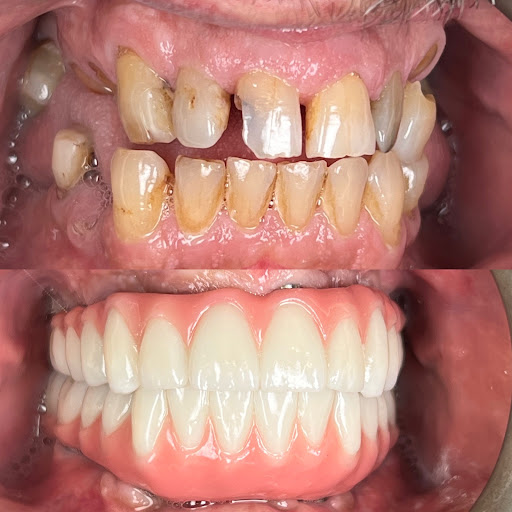

Photos